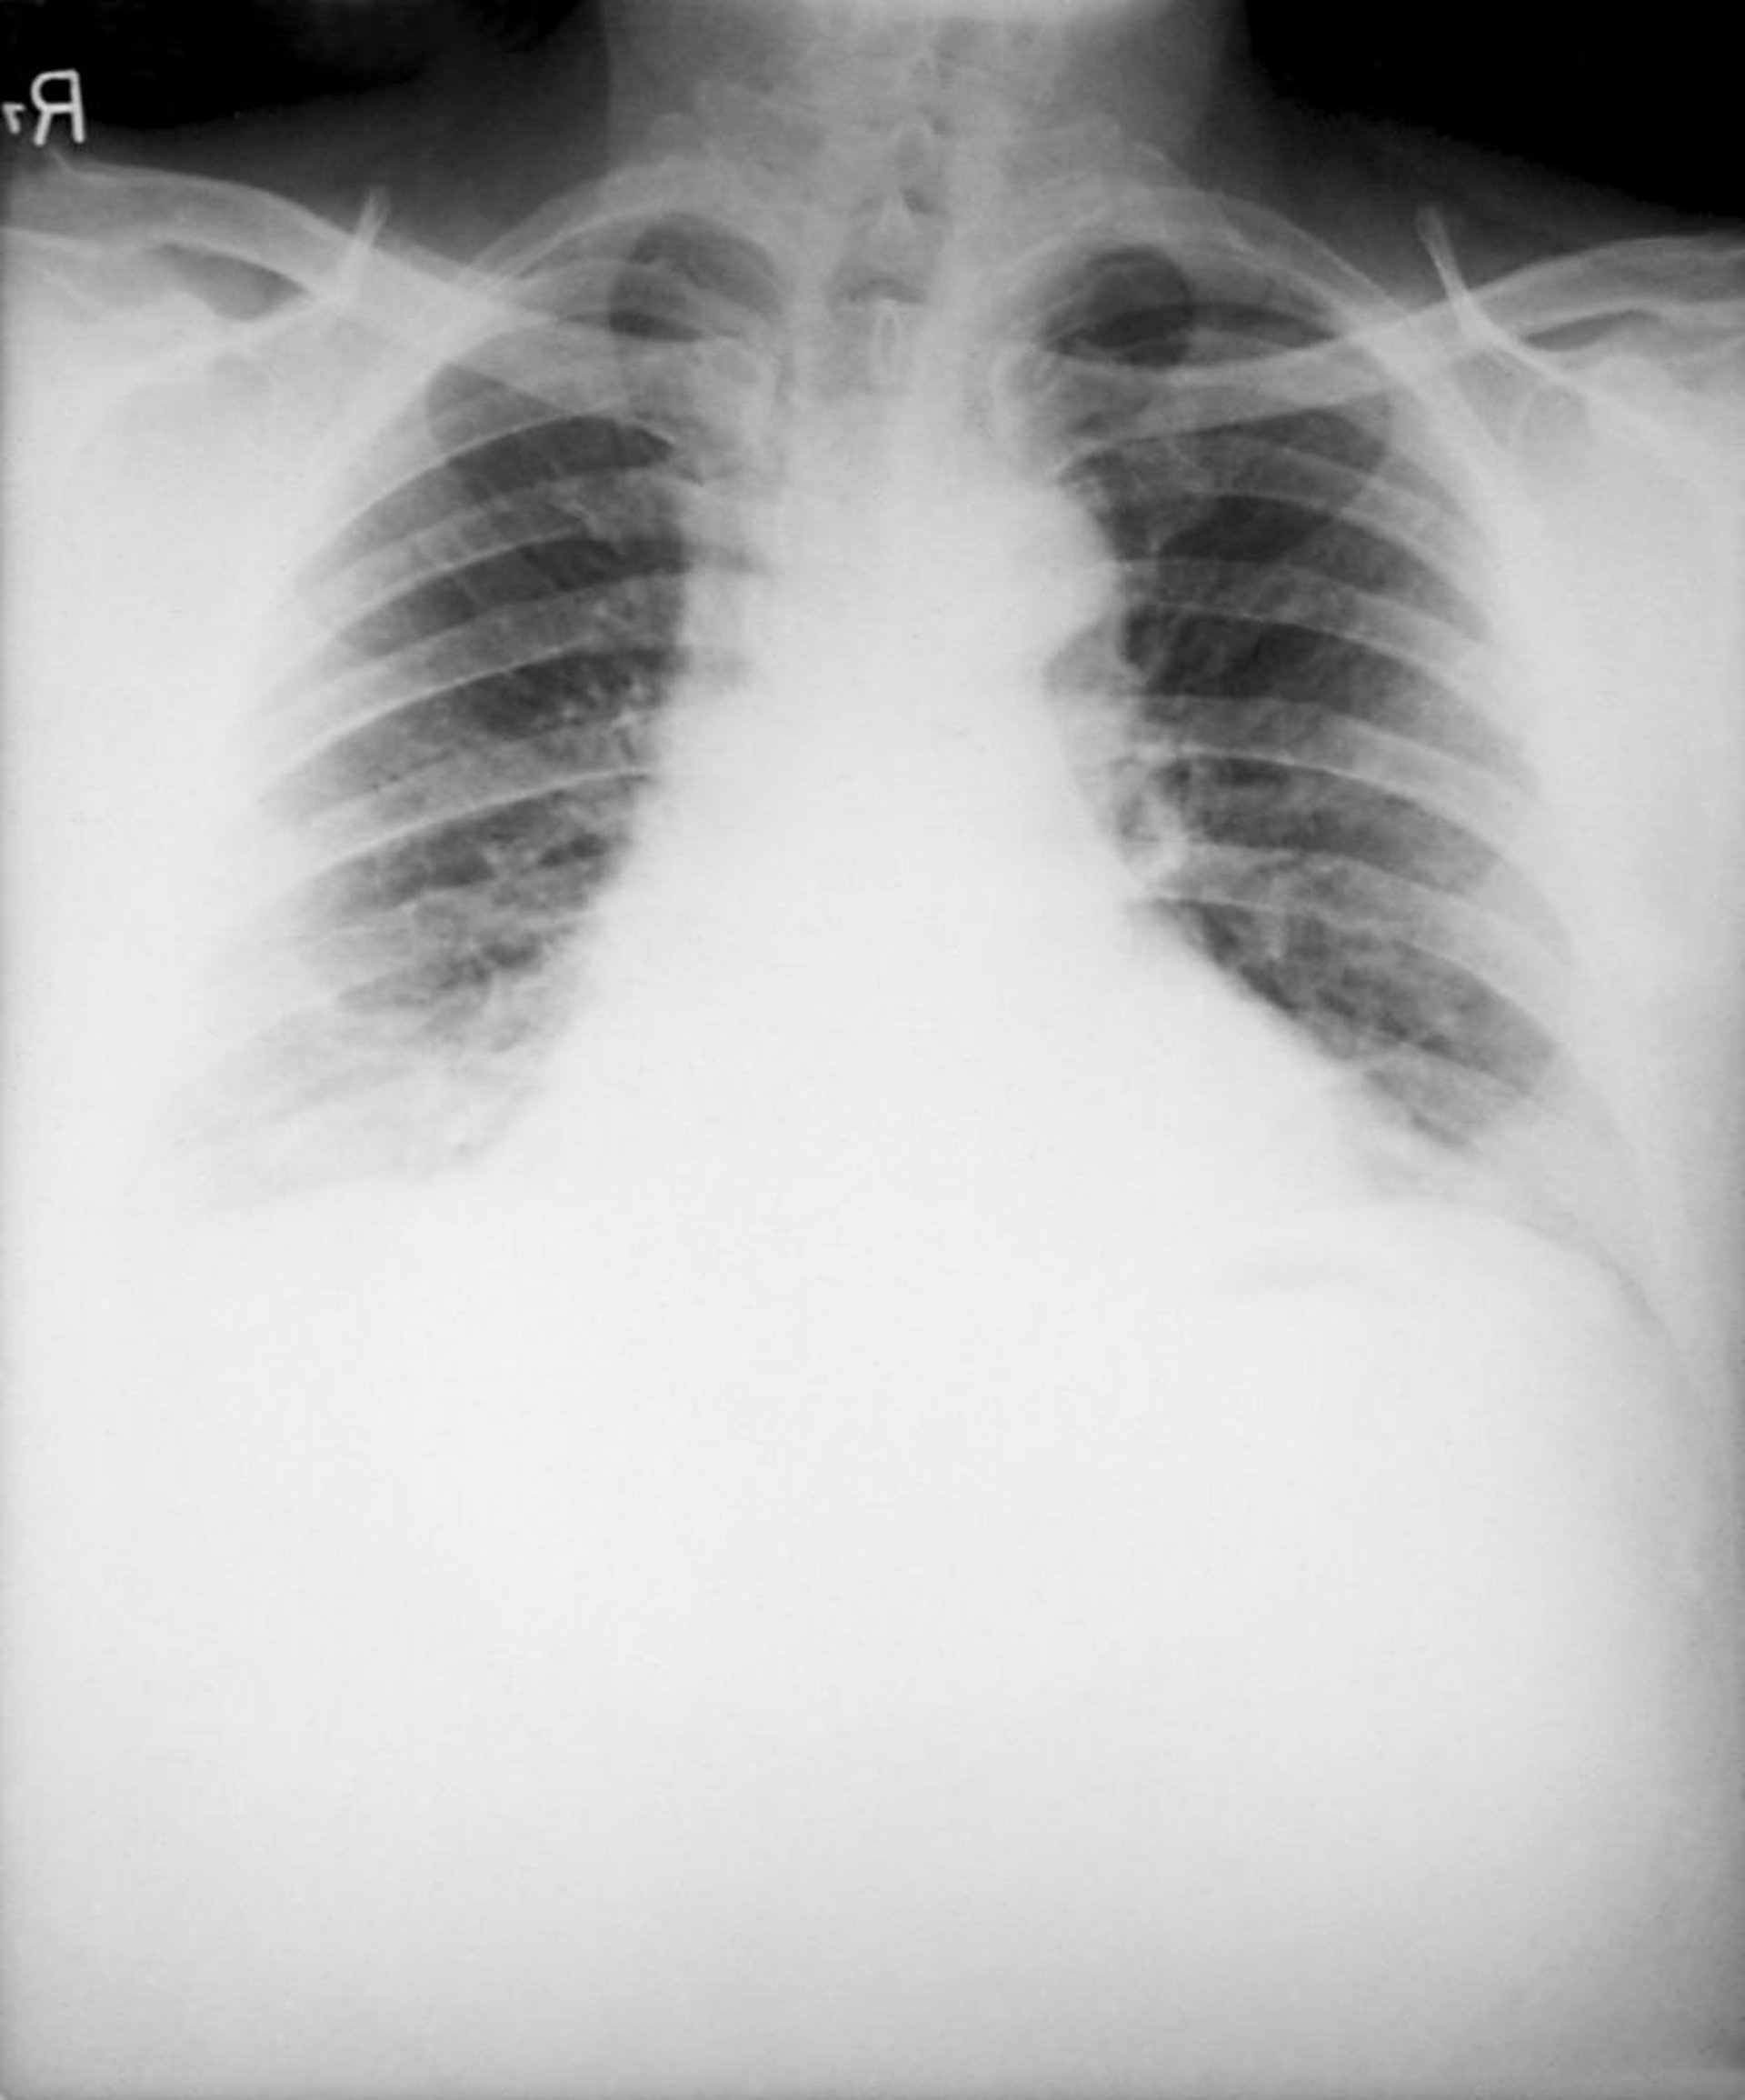

Carbunco (inhalación)

Los hallazgos típicos de ántrax por inhalación en la radiografía de tórax consisten en un ensanchamiento mediastínico causado por una linfadenitis mediastínica necrosante hemorrágica y la presencia de derrames pleurales bilaterales. Los infiltrados neumónicos son raros.

Image courtesy of the Public Health Image Library of the Centers for Disease Control and Prevention.